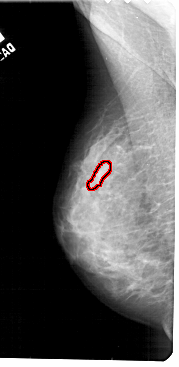

A_1783_1.LEFT_CC

LEFT_CC LINES 5296 PIXELS_PER_LINE 2566 BITS_PER_PIXEL 12 RESOLUTION 43.5 OVERLAY

FILE: A_1783_1.LEFT_CC.OVERLAY

TOTAL_ABNORMALITIES 1

ABNORMALITY 1

LESION_TYPE CALCIFICATION TYPE PLEOMORPHIC DISTRIBUTION SEGMENTAL

ASSESSMENT 4

SUBTLETY 2

PATHOLOGY BENIGN

TOTAL_OUTLINES 1

BOUNDARY